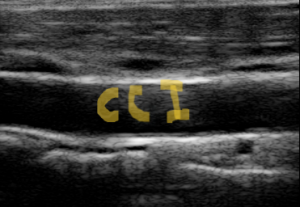

- Ecografía Doppler de vasos cervicales Arteria carotidas (útil para descartar patología vascular).

|